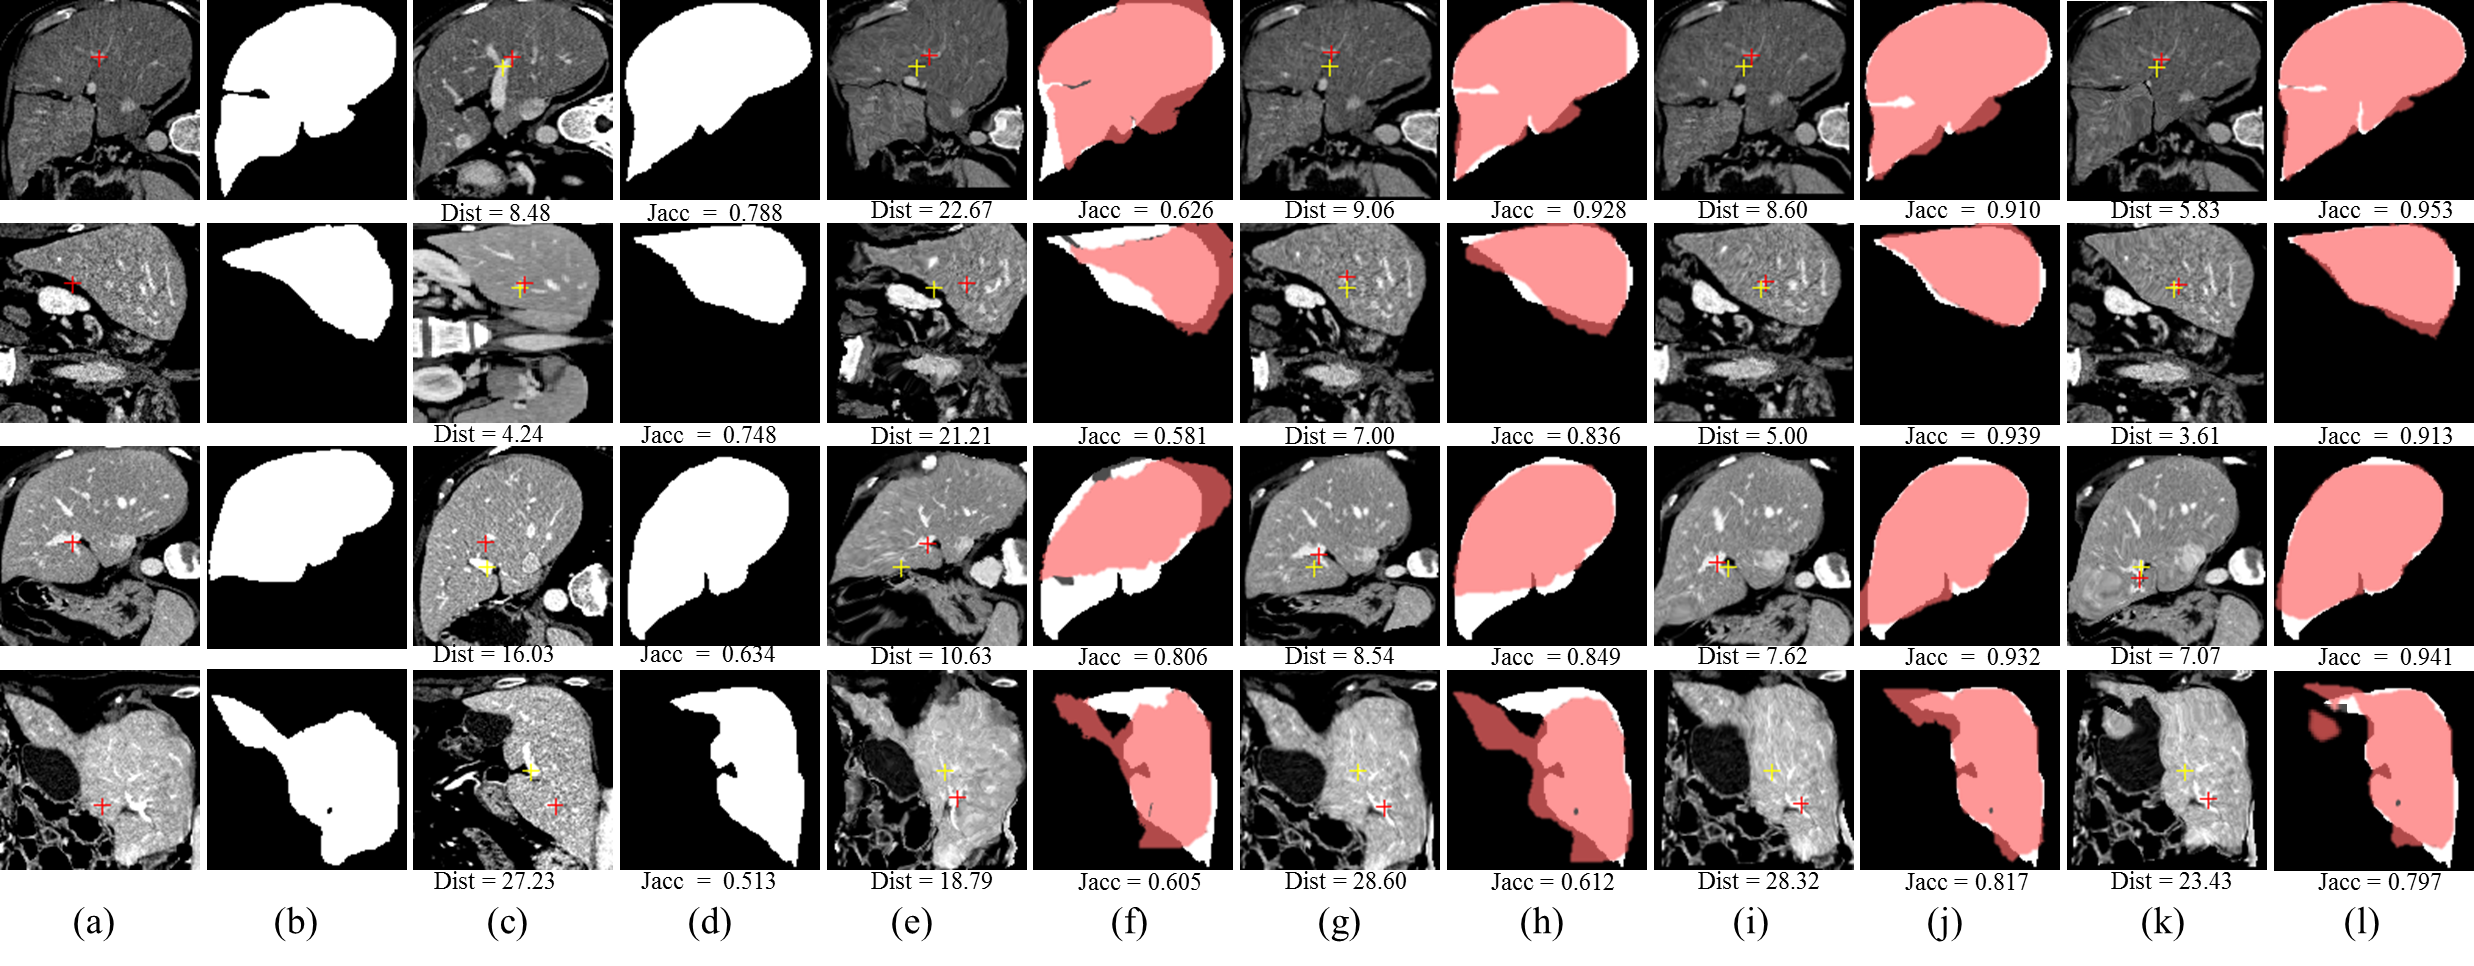

IV-G2 Experiment Results

Trifold cross validation is adopted in the experiment and the results are reported only on the 3,672 (18×\times17×\times4×\times3×\times1) 2D slice pairs containing the same corresponding landmarks. Table III quantitatively shows the performance of our unsupervised methods, our best baseline (supervised methods) and the best traditional registration algorithms. We retrain the unsupervised PN and PE model with this enlarged dataset and obtain an improvement on the registration performance. Notably, Dist of PE model decreases from 13.79 to 13.54 and Jacc increases from 0.837 to 0.845, as is shown in Table III. Figure 7 illustrates the registration results of different methods.

Figure 7: Illustration of the liver registration performance of the proposed unsupervised methods, our best supervised baseline (w/ mask) methods and one the best traditional registration algorithms (Elastix) with the best Dist: (a) Moving image, (b) Ground truth segmentation mask of moving image, (c) Fixed image, (d) Ground truth segmentation mask of fixed image. (e), (g), (i) and (k) respectively denote the moving images warped by the best traditional registration algorithm (elastix), our best supervised baseline method (itk16), our best unsupervised method PN. The translucent red masks in (f), (h), (j), (l) respectively correspond to (e), (g), (i), (k) and denote the warped ground truth segmentation mask of the moving images. The white masks in (f), (h), (j), (l) are the ground-truth segmentation mask of the fixed image. The red and yellow crosses denote landmarks of moving image and fixed image, respectively. Dist in (c) and Jacc in (d) denote no registration.